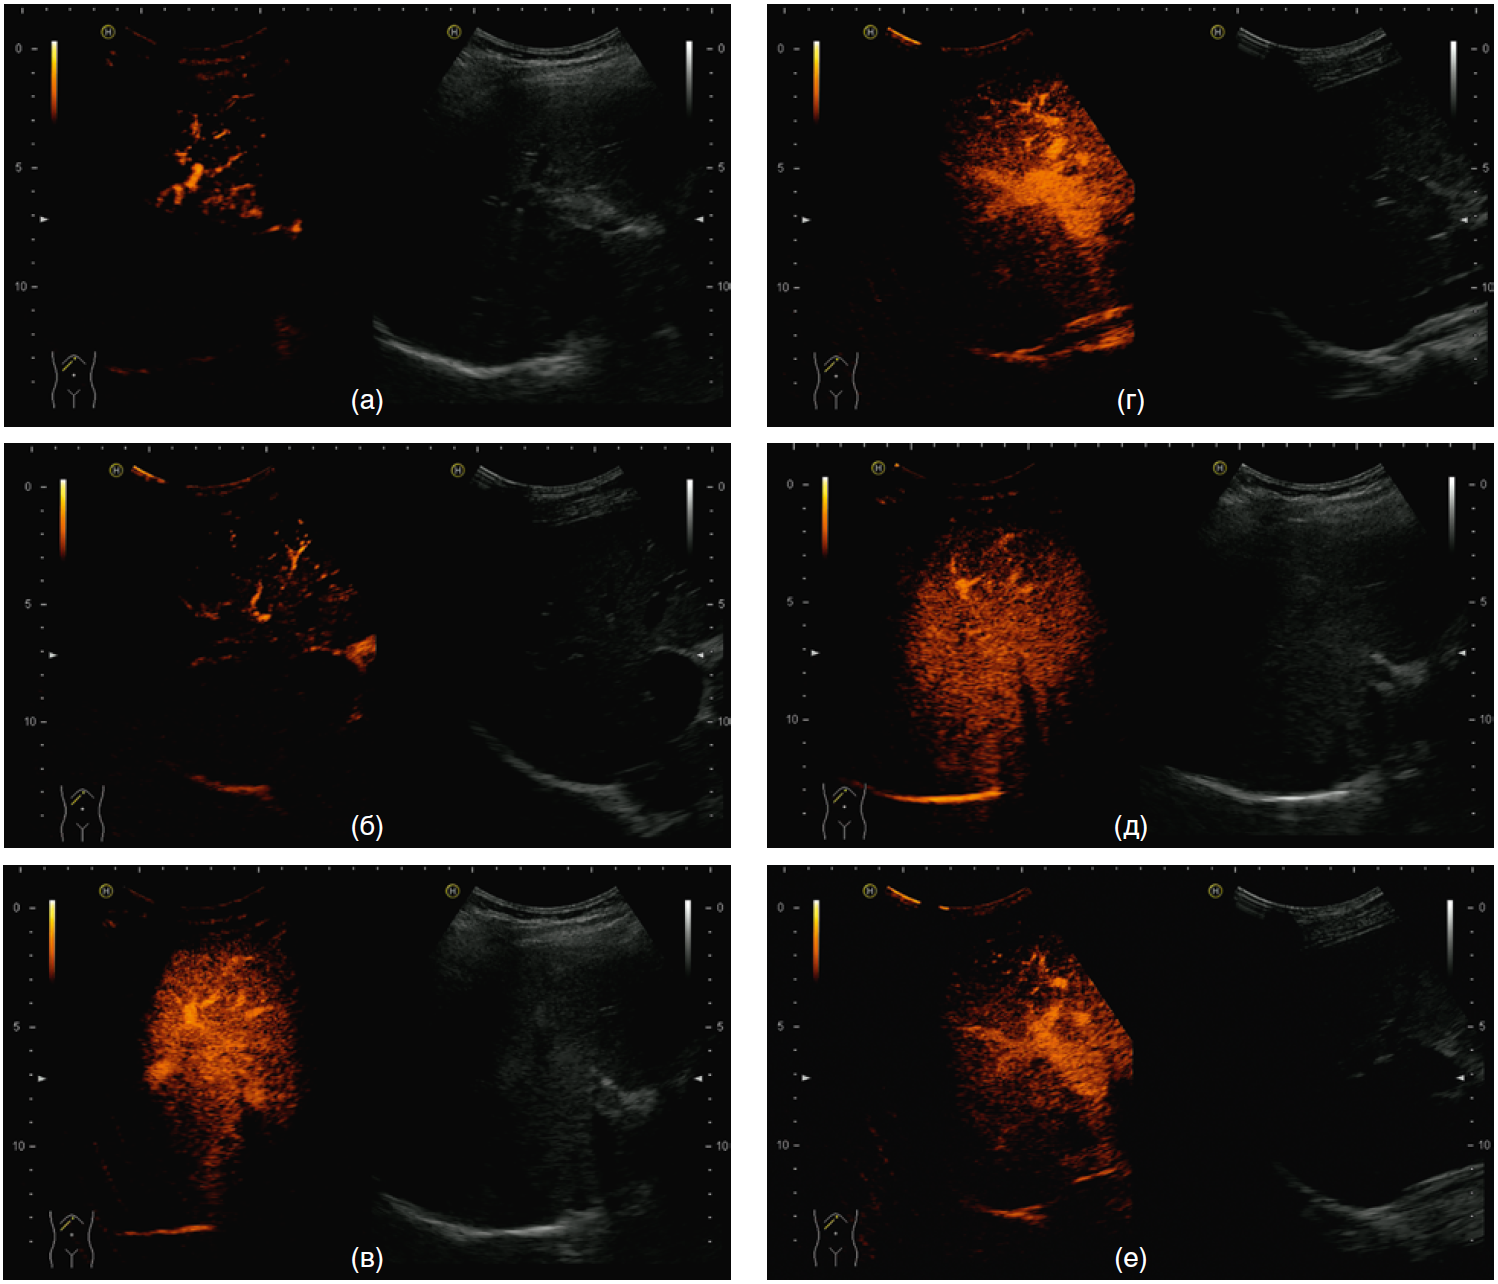

Качественные показатели КУУЗИ у пациентов различных групп (2,5 и 1,0 мл контрастного препарата) отражены на рис. 2, 3, при этом качество изображений, полученных при введении 1,0 мл контрастного препарата, было идентично или несколько ниже, чем при введении 2,5 мл, но достаточным для оценки.

Рис. 2. Качественная оценка контрастно-усиленного ультразвукового исследования печени при введении 2,5 и 1,0 мл контрастного препарата: патологии не выявлено

Примечание. а — артериальная фаза, 2,5 мл; б — артериальная фаза, 1,0 мл; в — портальная фаза, 2,5 мл; г —портальная фаза, 1,0 мл; д — поздняя венозная фаза, 2,5 мл; е — поздняя венозная фаза, 1,0 мл.